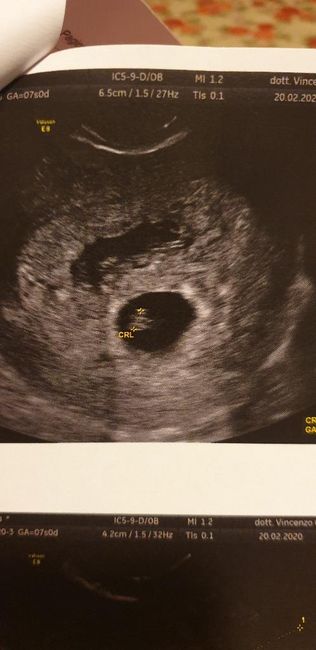

2262 giorni faEcco il primo esame del beta! Nella range di riferimento del laboratorio sono nella norma, però leggendo i vari forum mi sembra bassino rispetto ai valori delle altre mamme. L'ultimo ciclo l ho avuto l'1 gennaio (quindi sarei a 5+1) ma l'ovulazione...